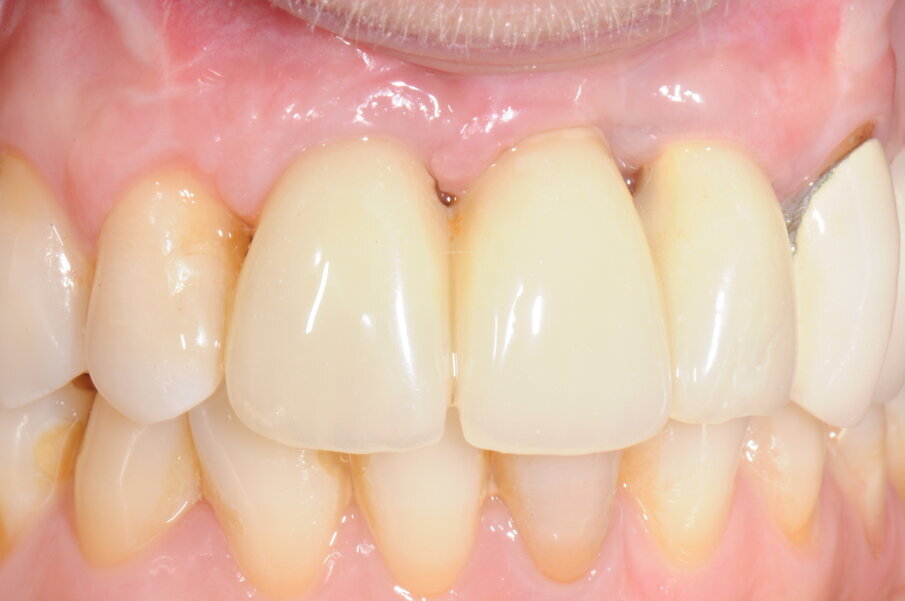

La paziente, donna, di anni 55, era giunta alla nostra osservazione richiedendo una riabilitazione protesica in area estetica a seguito di trauma provocato da un incidente stradale, avvenuto da circa 10 anni, che aveva determinando la perdita di due incisivi superiori in posizione 2.1, 2.2 (Figg. 1, 2).

Fig. 1 - Situazione iniziale della paziente al momento della prima visita.

Fig. 2 - Visione frontale della zona edentula.